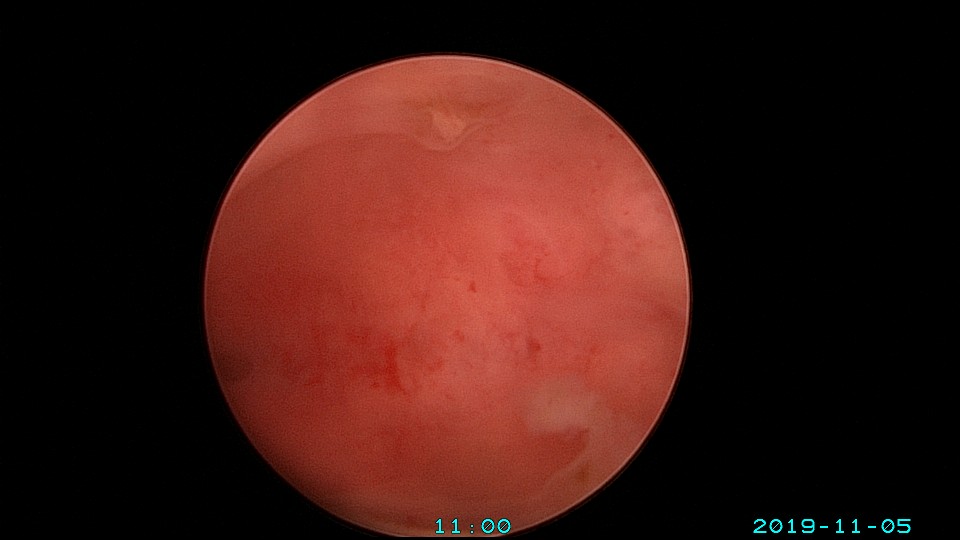

患者26岁,G1P0 ,2019年9月门诊宫腔镜检查发现宫腔重度粘连,2019年10月住院宫腔镜分粘,恢复宫腔形态,显露双侧输卵管开口。2019年11月宫腔镜二探取球囊,宫腔形态正常,双侧输卵管开口可见。2021年3月发现自然妊娠,后因先兆流产、胎心弱在当地医院险些清宫终止妊娠,病人电话咨询我,嘱病人千万不要急着清宫,立即到我院复查,心管搏动良好,住院保胎成功,2021年11月,39周孕剖宫产分娩。2023年7月,再次自然妊娠,39+3周孕剖宫产分娩。现31岁,G3P2。